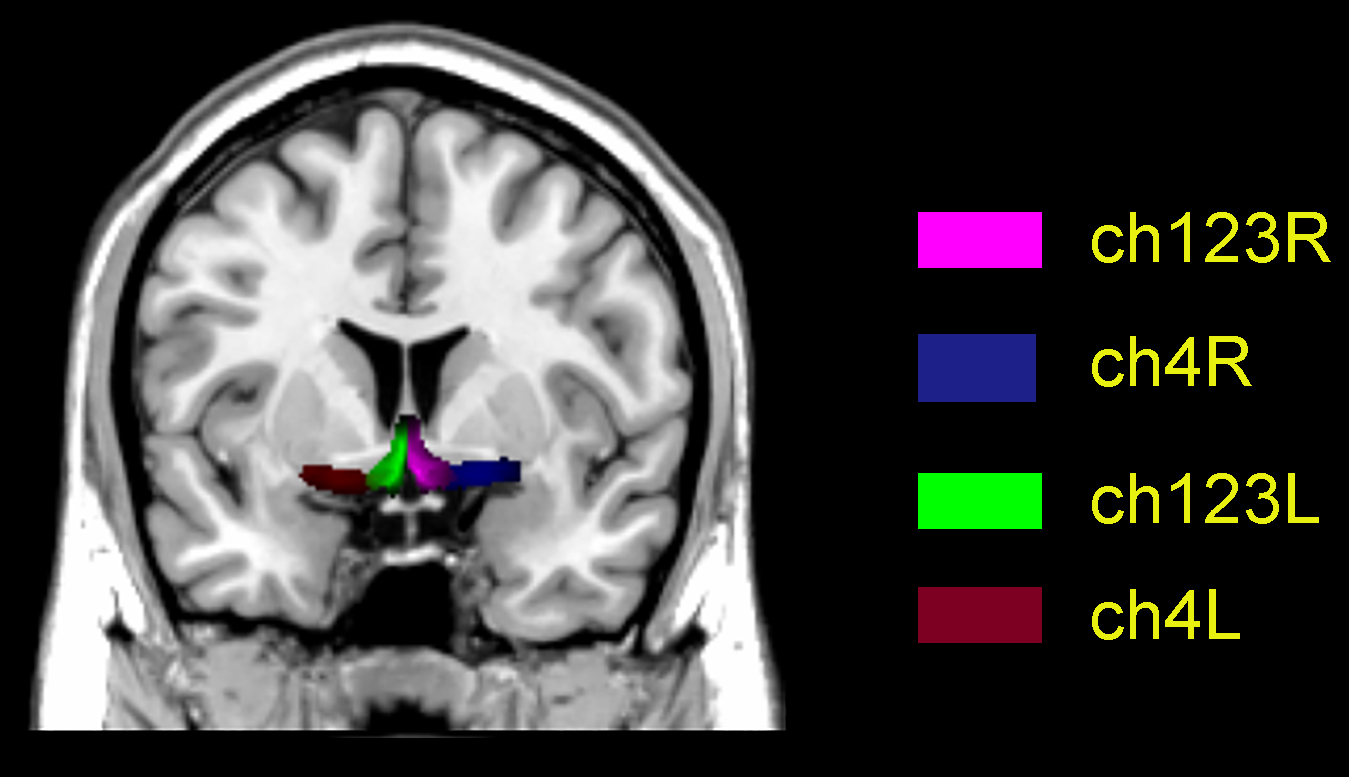

Functional connectivity analysis was performed using four BF seeds per participant, defined according to the Julich-Brain Atlas [15] (Fig. 1, Ref. [16]): bilateral cholinergic cell group (Ch)123 (medial septum/diagonal bands) and bilateral Ch4 (NBM). Whole-brain connectivity maps were generated for each seed using Pearson correlation, followed by Fisher’s r-to-z transformation to z scores for normalization.

Fig. 1.

Basal forebrain subregion map on a Montreal Neurological Institute (MNI) template. Ch123L/R denote left/right medial septum/diagonal bands; Ch4L/R denote left/right nucleus basalis of Meynert. Ch, cholinergic cell group. [16].